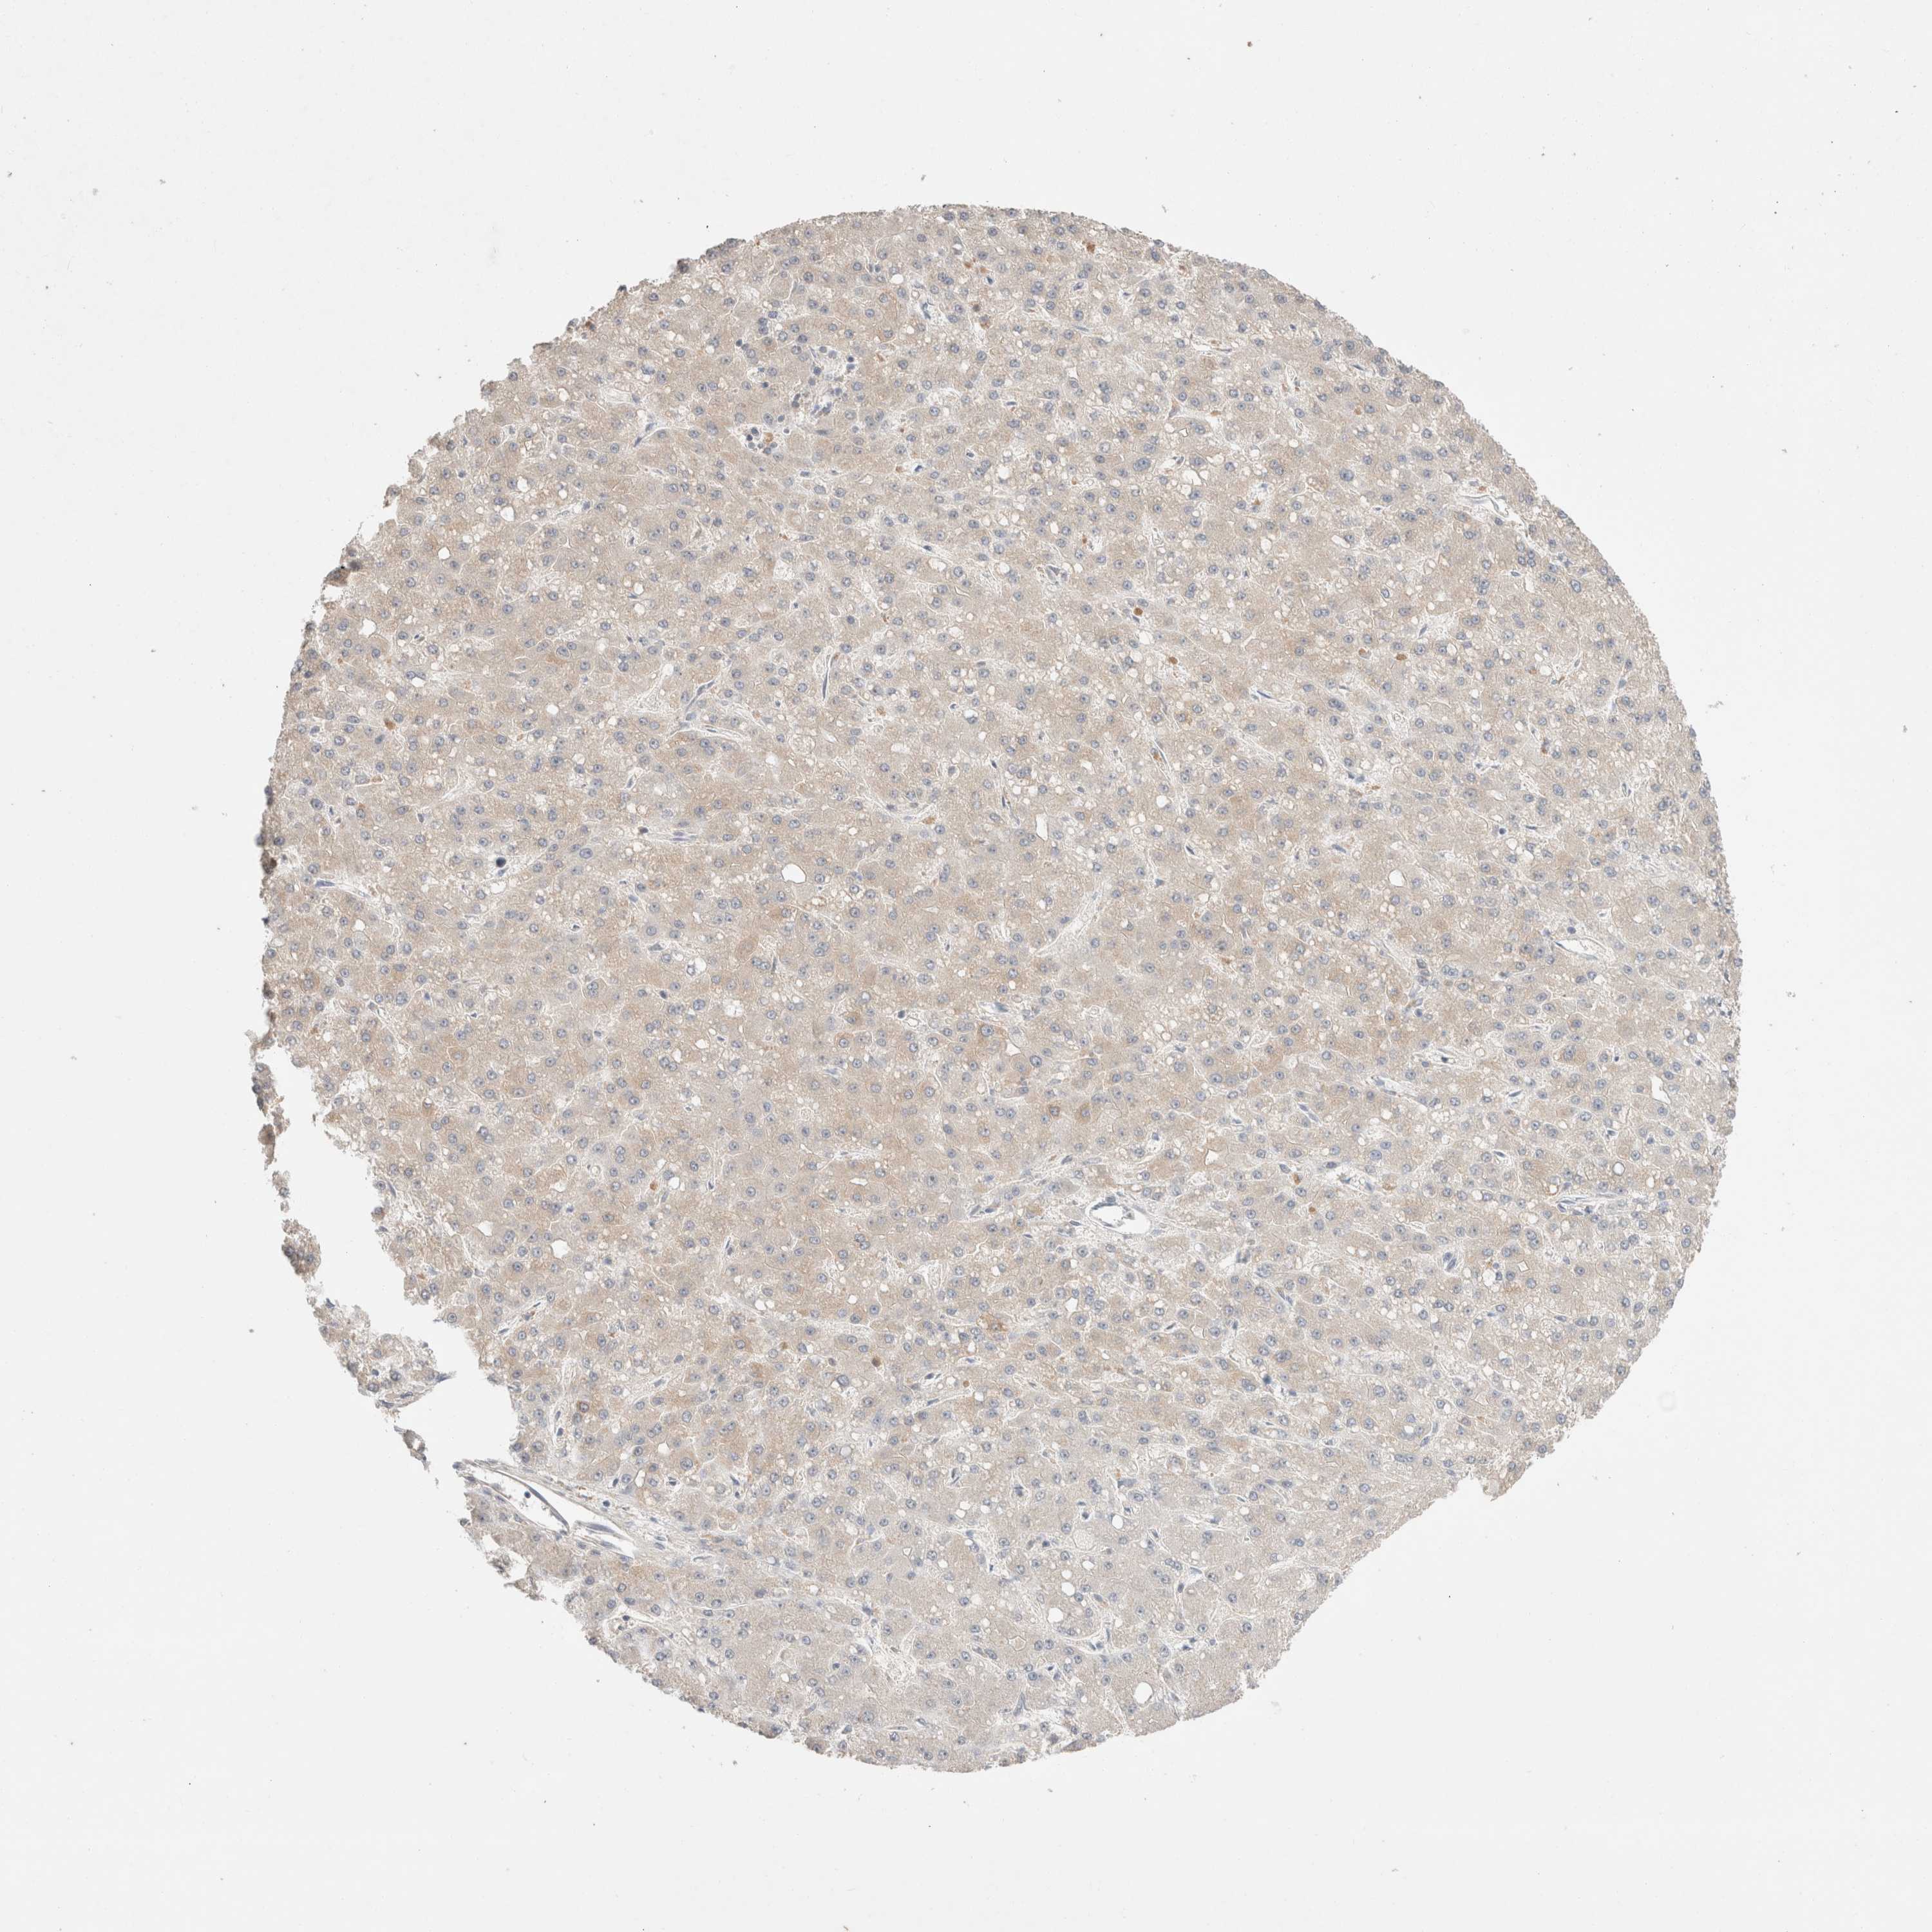

LIVER CANCER - Protein expressioni

A mouse-over function shows sample information and annotation data. Click on an image to view it in a full screen mode. Samples can be filtered based on level of antibody staining by selecting one or several of the following categories: high, medium, low and not detected. The assay and annotation is described here.

Note that samples used for immunohistochemistry by the Human Protein Atlas do not correspond to samples in the TCGA dataset.

Antibody stainingi

Antibody staining in the annotated cell types in the current human tissue is reported as not detected, low, medium, or high, based on conventional immunohistochemistry profiling in selected tissues. This score is based on the combination of the staining intensity and fraction of stained cells.

Each image is clickable and will lead to virtual microscopy that enables deeper exploration of all samples and also displays staining intensity scores, fraction scores and subcellular localization as well as patient and tissue information for each sample.

Antibody HPA024204

Staining

High

Medium

Low

Not detected

Intensity

Strong

Moderate

Weak

Negative

Quantity

>75%

75%-25%

<25%

None

Location

Nuclear

Cytoplasmic/membranous

Cytoplasmic/membranous,nuclear

Cholangiocarcinoma

Carcinoma, Hepatocellular, NOS